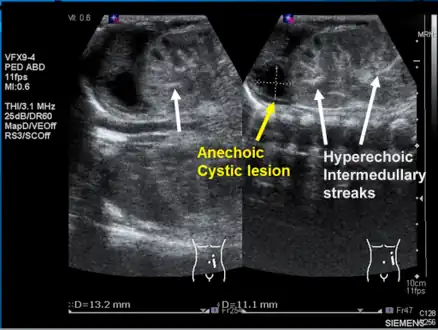

Left kidney with a suprarenal anechoic cyst-like lesion and hyperechoic intermedullary streaks in initial phase of renal vein thrombosis -

Observing the patient's symptoms, medical history and imaging remain the fundamental source for diagnosing RVT. Imaging is used to detect the presence of a blood clot. In an abnormal kidney with RVT, a blood clot is present in the renal vein. In cases where the renal vein is suddenly and/or fully blocked, the kidneys will enlarge, reaching its maximum size within a week. An ultrasound imaging can be used to observe and track the size of the kidneys in RVT patients. Ultrasound is not efficient for use in detecting blood flow in the renal veins and artery. Instead a color doppler ultrasound may be used to detect renal blood flow. It is most commonly used to detect RVT in patients who have undergone renal transplantation. CT angiography is currently the top choice in diagnosing RVT. It is non-invasive, relatively cheap and fast with high accuracy. CT scanning can be used to detect renal enlargement, renal tumors, blood flow and other renal pathologies. An alternative is magnetic resonance angiography or MRA. It is non-invasive, fast and avoids radiation (unlike a CT scan) but it is relatively expensive. MRA produces detailed images of the renal blood flow, vesicle walls, the kidneys and any surrounding tissue. An inferior venocavography with selective venography can be used to rule out the diagnoses of RVT.[6]